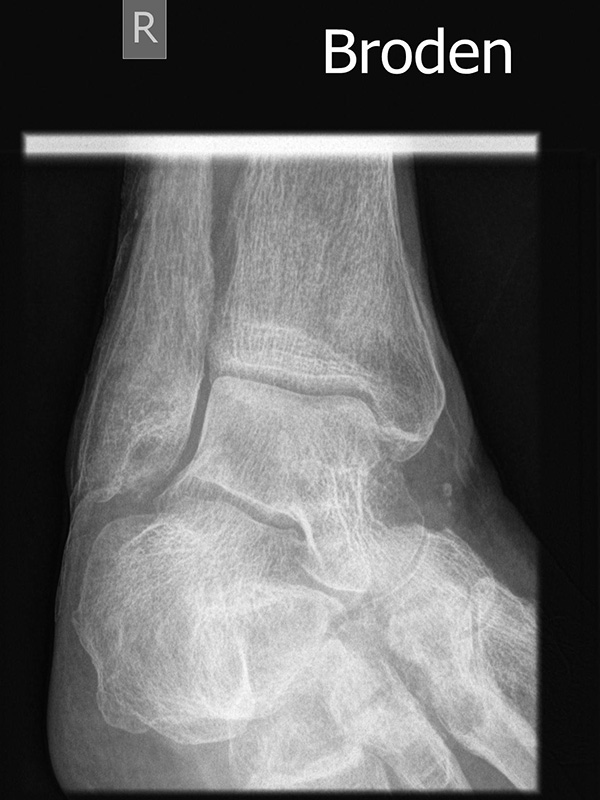

Broden-Aufnahme

Broden-Aufnahme Innenrotation

Indikation:

• Darstellung der dorsalen Facette des Subtalargelenks in verschiedenen Projektionen.

• Die Aufnahme wurde durch CT und DVT weitgehend abgelöst.

• Broden-Projektionen werden intraoperativ zur Beurteilung der Rekonstruktion der dorsalen Gelenkfacette bei Kalkaneusfrakturen verwendet.

Positionierung:

• Patient in Rückenlage, Fuß in Innenrotation (45°), Sprunggelenk im 90°-Winkel abgewinkelt, ggf. gelagert auf einem Schaumstoffkeil.

• Filmposition horizontal am Röntgentisch.

• Zentralstrahl verläuft je nach angefordeter Gradzahl 10°, 20°, 30°, und oder 40° caudo-cranial auf das untere Sprunggelenk.

Kennzeichen des Röntgenbildes:

• Gute Einsicht in den hinteren unteren Sprunggelenkabschnitt durch unterschiedliche Projektionen.

• Überlagerungsfreie Darstellung des Außenknöchels und der tibiofibularen Syndesmose.

Besondere Bemerkungen zum Beispielbild:

• Brodenaufnahme 10°.

• Initiale degenerative Veränderungen im Subtalargelenk.

• Impression der lateralen Gelenkfläche des Kalkaneus.

Zur Vollansicht und zum Lesen der Bildbeschreibung bitte das Bild anklicken.